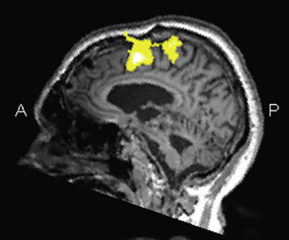

Brain injury such as following traffic or sports accidents can lead to severe disorders, including disorders of consciousness. This disorder is currently diagnosed through behavioural assessments, but this method fails when patients are not able to respond overtly. We investigated whether neural responses to speech as measured from the clinically-applicable EEG can aid to diagnose disorders of consciousness. We focussed on the neural tracking of the speech envelope that can index attention to speech as well as speech comprehension. We find that the latency of the neural envelope tracking related to the severity of the disorder of consciousness: patients in a vegetative state without signs of consciuosness showed neural responses to the speech envelope that were significantly delayed compared to patients that exhibited consciusness.

Cortical Response to the Natural Speech Envelope Correlates with Neuroimaging Evidence of Cognition in Severe Brain Injury,

Curr. Biol. 28:1-7 (2018). [pdf]